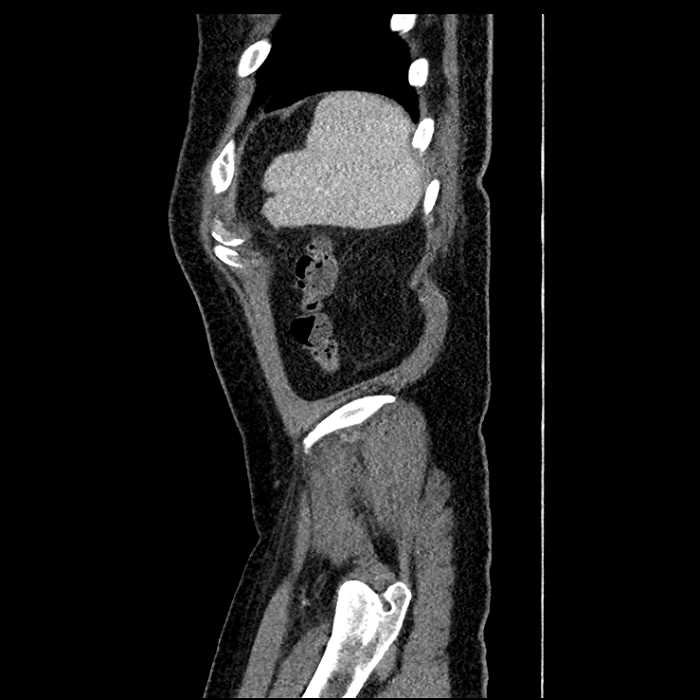

• Large fluid density structure in hepatic segments 7 and 8 measuring 10 x 7 x 7 cm with internal septation and circumferential ill-defined low density compatible with edema

• Peripherally enhancing subcapsular collections along the anterior margin of the left hepatic lobe measuring 3 x 1 cm and 2 x 1 cm

• Clearly marginated fluid density structure in segment 7 and several other scattered tiny hypodensities, which likely represent cysts

Acute sigmoid diverticulitis complicated by a small contained perforation and a large abscess in the right hepatic lobe. Additional small subcapsular abscesses along the anterior margin of the left hepatic lobe.

• The classic CT imaging appearance is a double target sign with internal low density surrounded by an internal enhancing rim (capsule) and a low density external rim (edema)

• Abscesses may be unilocular or multilocular

Hepatic abscess showing the double target sign with low density internally surrounded by a thin inner enhancing rim (red arrow) and ill-defined outer low density rim (yellow arrow). Blue arrow indicates an internal septation. Red arrows: additional smaller subcapsular abscesses. Red arrow: focal contained perforation associated with diverticulitis.